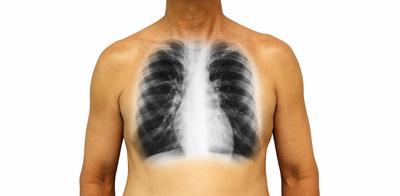

健康人的胸膜腔为负压(呼吸时平均为-5cmH2O,1cmH2O=98Pa),胸液中含蛋白质,具有胶体渗透压(8cmH2O)。胸液的积聚与消散亦与胸膜毛细血管中渗透压、静水压有密切关系。壁层胸膜由体循环供血,毛细血管静水压高(30cmH2O);脏层胸膜则由肺循环供血,静脉压低(11cmH2O)。体循环与肺循环血膜以相等速度被吸收。

根据动物实验测算,人体每天胸膜腔可有0.5~1L液体通过。胸液中的蛋白质主要经由淋巴管进入胸导管。

胸膜炎症可使管壁通透性增高,较多蛋白质进入胸膜腔,使胸液渗透压增高。肿瘤可压迫、阻断淋巴引流,致使胸液中蛋白质积累,导致胸腔积液。门静脉肝硬化常有低蛋白血症,血浆胶质渗透压降低,可产生漏出液,当有腹水时,又可通过膈肌先天性缺损或经淋巴管而引起胸腔积液。变态反应性疾病、自身免疫病、心血管疾病或胸外伤等,增有可能产生胸腔积液。